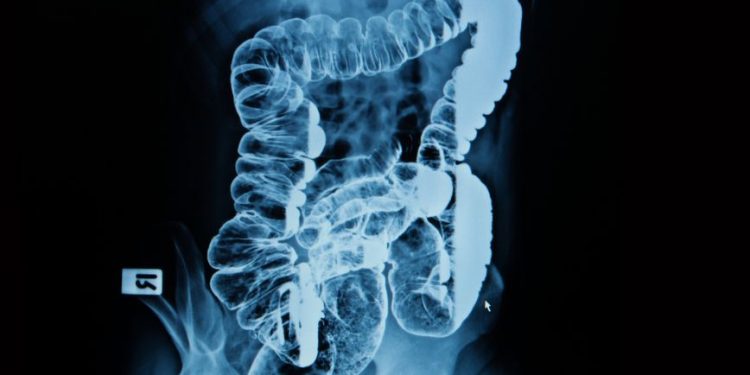

In some cases, a patient may undergo a CT scan to determine whether there is a problem with the arteries. Other tests that may be performed to confirm the diagnosis of mesenteric ischemia include magnetic resonance angiography. The images produced by the scan can be very detailed. The arteries are identified, as are the abdominal organs.